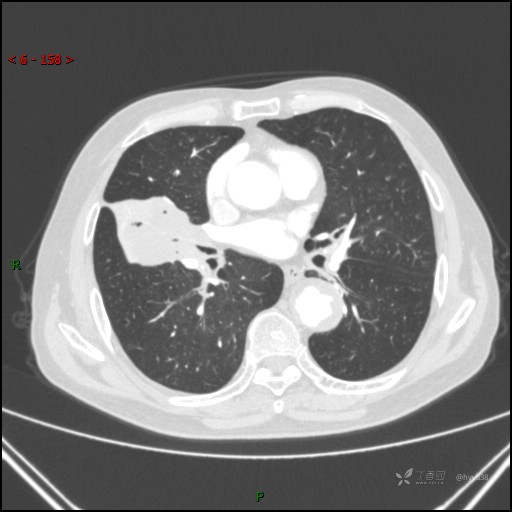

静脉期